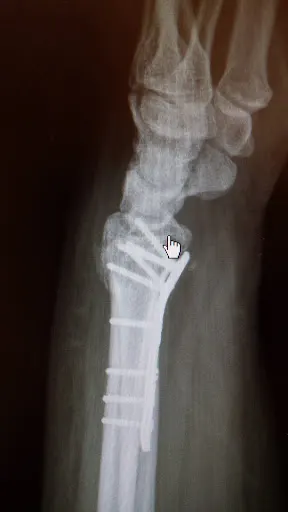

FilMedica Filipczak to specjalistyczna klinika medyczna zlokalizowana w Ciechanowie przy ul. Maksymiliana Marii Kolbe 68. Placówka oferuje usługi w zakresie ginekologii i położnictwa, ortopedii oraz fizjoterapii urologicznej, skupiając się na kompleksowej opiece dla pacjentów z regionu. Z oceną 4.5 na 5 w Google na podstawie 28 opinii, klinika cieszy się uznaniem wśród lokalnej społeczności, która docenia przede wszystkim profesjonalizm lekarzy. Pacjenci chwalą lekarzy takich jak Tomasz Filipczak, specjalista od ortopedii, za skuteczne leczenie i miłą atmosferę, oraz Elżbietę Filipczak i Katarzynę Grądzką z ginekologii za empatyczne podejście, dokładne badania i prowadzenie ciąż. Wielu podkreśla rzetelność, szczegółowe wyjaśnienia i zaangażowanie personelu medycznego, co zmienia postrzeganie lokalnej opieki zdrowotnej w porównaniu do wyjazdów do Warszawy. Klinika jest polecana szczególnie kobietom w ciąży i osobom z problemami ortopedycznymi. Choć pojawiają się uwagi krytyczne wobec obsługi recepcji i sporadycznych opóźnień, ogólny odbiór wskazuje na solidny poziom usług. FilMedica Filipczak stanowi wygodną opcję dla mieszkańców Ciechanowa szukających specjalistycznej pomocy bez dalekich podróży. (198 słów)

- Skuteczne leczenie i operacje, np. małoinwazyjne kolana